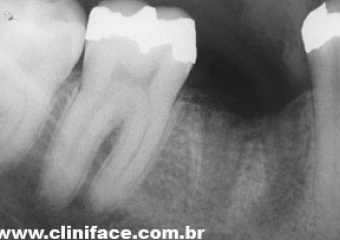

Raio X após a extração do dente comprometido